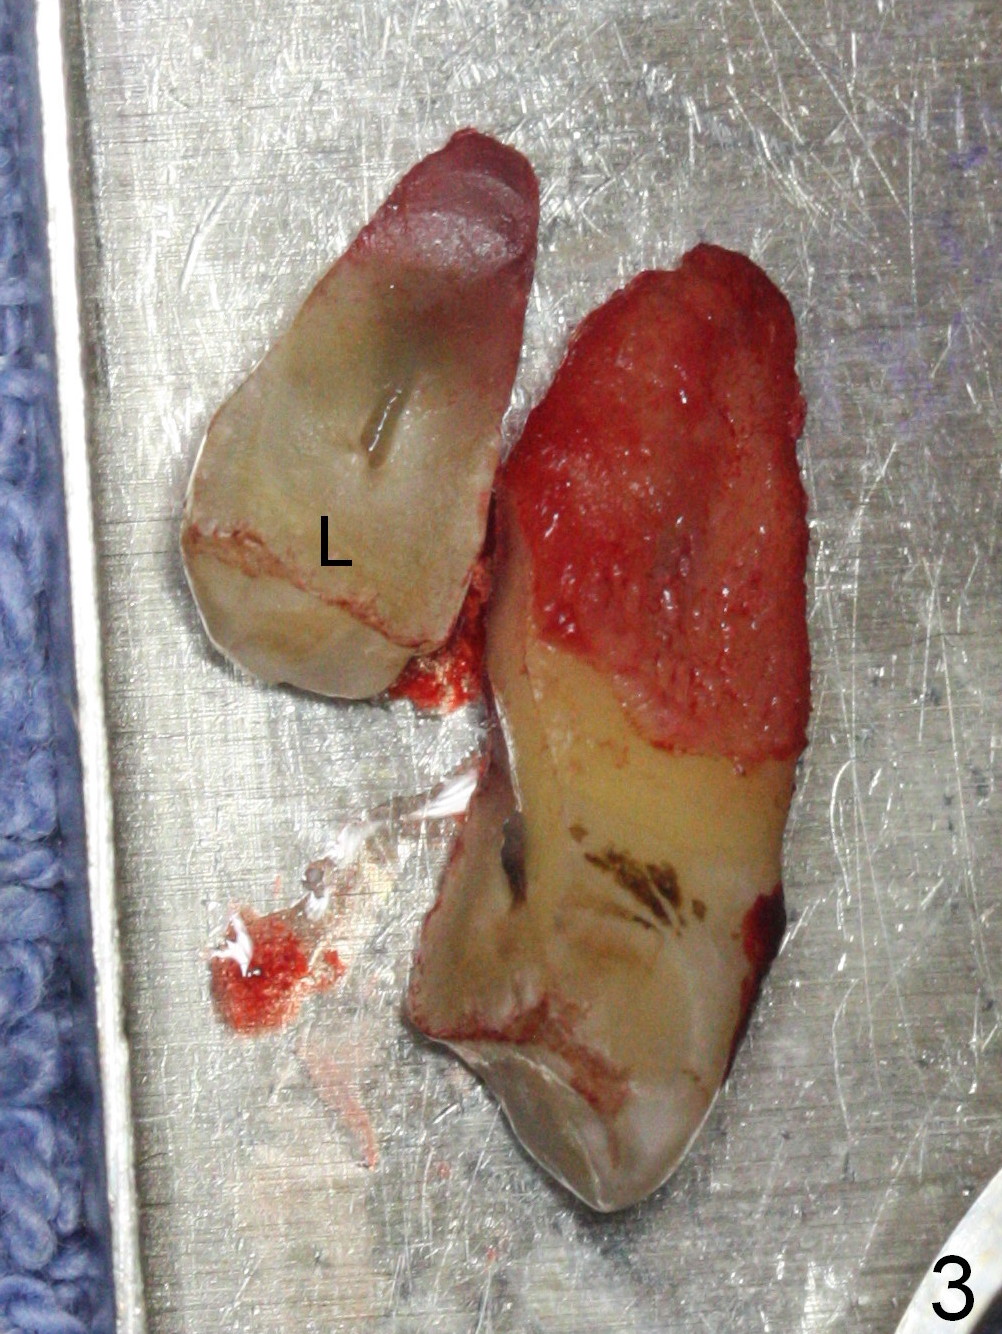

A 47-year-old man returns emergently with subgingival fracture of the lingual (L) cusp of the tooth #4 (Fig.1-3). After extraction (no bony defect) without drilling, a 4x11 mm dummy implant is placed as a tap drill with satisfactory stability (Fig.4,5). To get subcrestal placement, a shorter (4x9 mm) implant is inserted with insertion torque of < 35 Ncm. In retrospect, a larger implant (4.5 mm) would be better in term of primary stability. After allograft placement into the buccal and lingual gaps, a 4.5x4(4) mm abutment is placed for an immediate provisional. There is a peri-implant gap 7 months postop (Fig.7<, as compared to the implant at #2 (6 months postop)) . When the loose abutment is being retightened, the patient feels pain, although the gingiva appears healthy (Fig.8). A larger implant should have been used; the abutment should have been removed. The implant dislodges while the abutment is untightened 8 months postop. The osteotomy is found intact. A 4.5x11 mm dummy implant is placed 2 mm subgingival with 20 Ncm (Fig.9). When a 4.5x11 mm definitive implant is placed 3 mm subgingival (Fig.10,11), torque reaches 50 Ncm. A 5.5x3 mm healing abutment is placed. Three months postop, the implant is stable (Fig.12,13) and impression is taken.